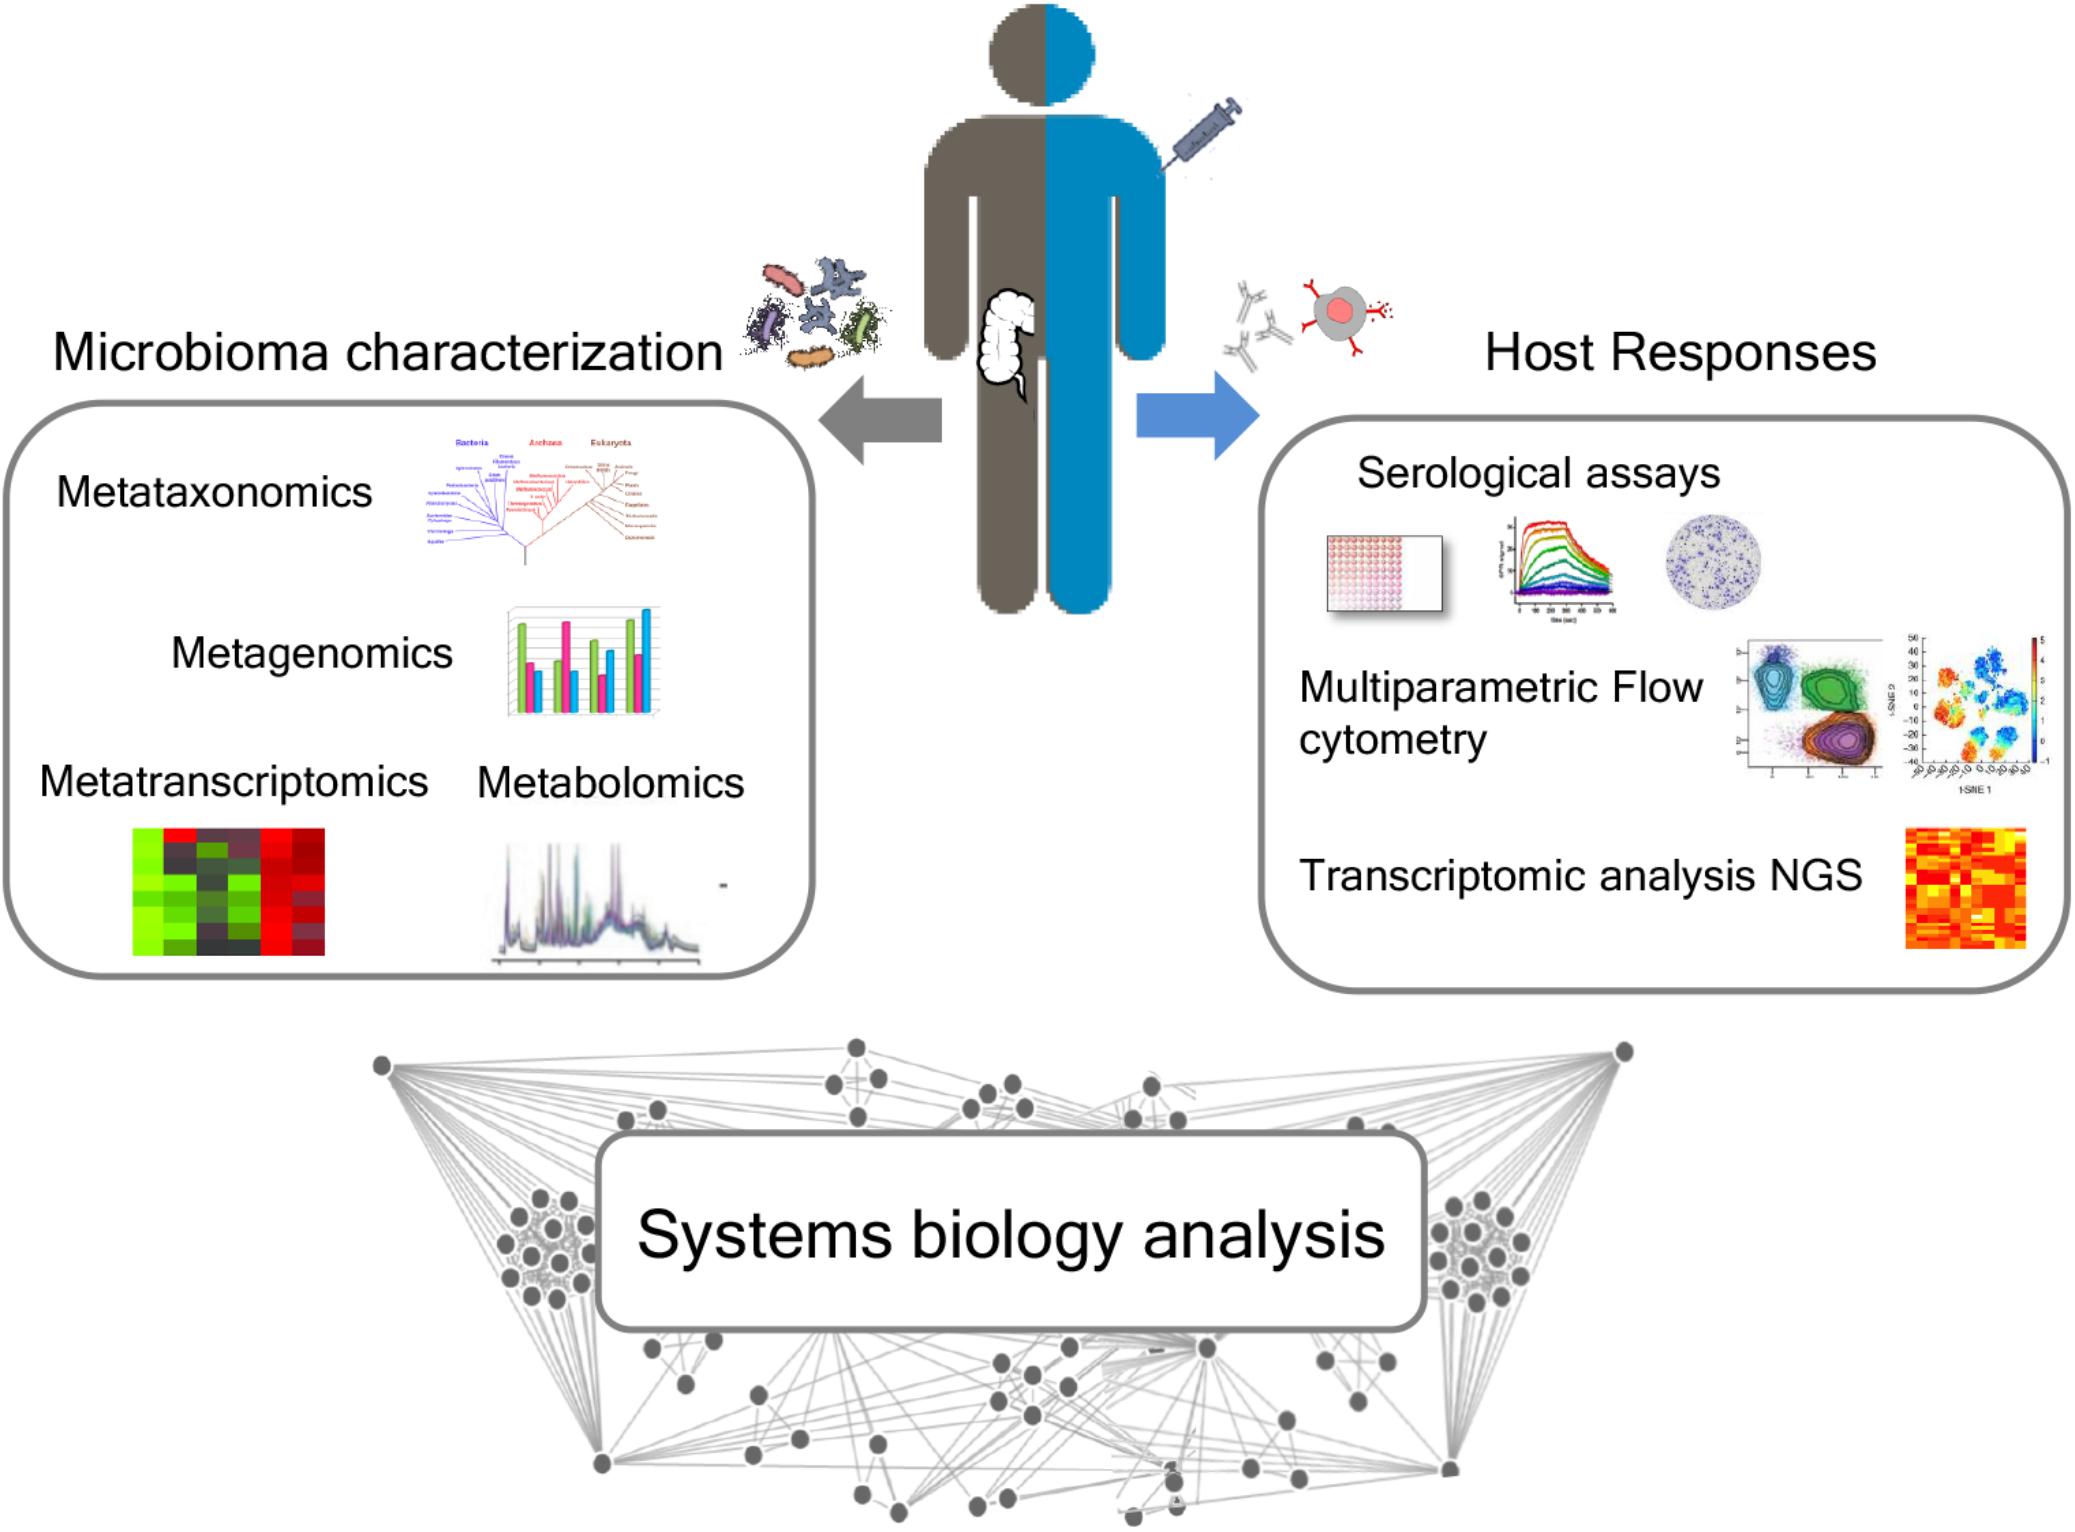

스트레스와 불안을 유발하는 근본 원인을 해결하기 위해 정신 건강에 미치는 세로토닌 등 호르몬 전구체를 만드는 장내세균 균형 복원을 위해 복합유익균 섭취와 균형잡힌 식사를 하는 것이 중요합니다. 균형잡힌 식사와 규칙적인 운동으로 신체가 건강해지면 불안도 줄고 가슴두근거림 증상도 가벼워질 수 있습니다.

연구에 의하면 장내세균 불균형으로 장내 유해세균 비율이 높은 상태가 지속되면 유해세균들이 만드는 독성이 뇌장축을 통해 뇌로 전달되어 우울증, 공황장애, 범불안장애, 불안증 등이 유발되고 가슴두근거림 증상 원인이 된다는 것입니다.

영양불균형과 장내세균 불균형을 바로잡아 장내 유익균을 복원하면 면역력 균형과 체력이 건강해져 백신 접종 후 가슴두근거림 증상 회복에 도움이 된답니다.

복합유익균과 유산균을 같이 먹어 장내세균 다양성을 복원하면 면역력 균형이 건강해져 독감(인플루엔자), 코로나19 백신 부작용도 없고 설령 코로나19나 독감에 감염되어도 무증상 또는 가벼운 증상만 겪고 완치된다는 연구가 있습니다.

장내세균 다양성을 유지하면 항체의 다양성이 합성돼서 다양한 항원인 백신을 맞아도 백신 부작용이 없거나 가볍다고 합니다